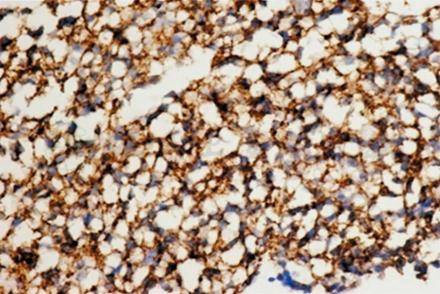

有时需用PCR技术来帮助诊断,特别困难的病例需骨髓穿刺,其标本再进行组织病理学(图4)和免疫组织化学检查(图5),明确诊断。

图5 骨髓穿刺组织标本免疫组化检查,瘤细胞CD138表达阳性IHC×400